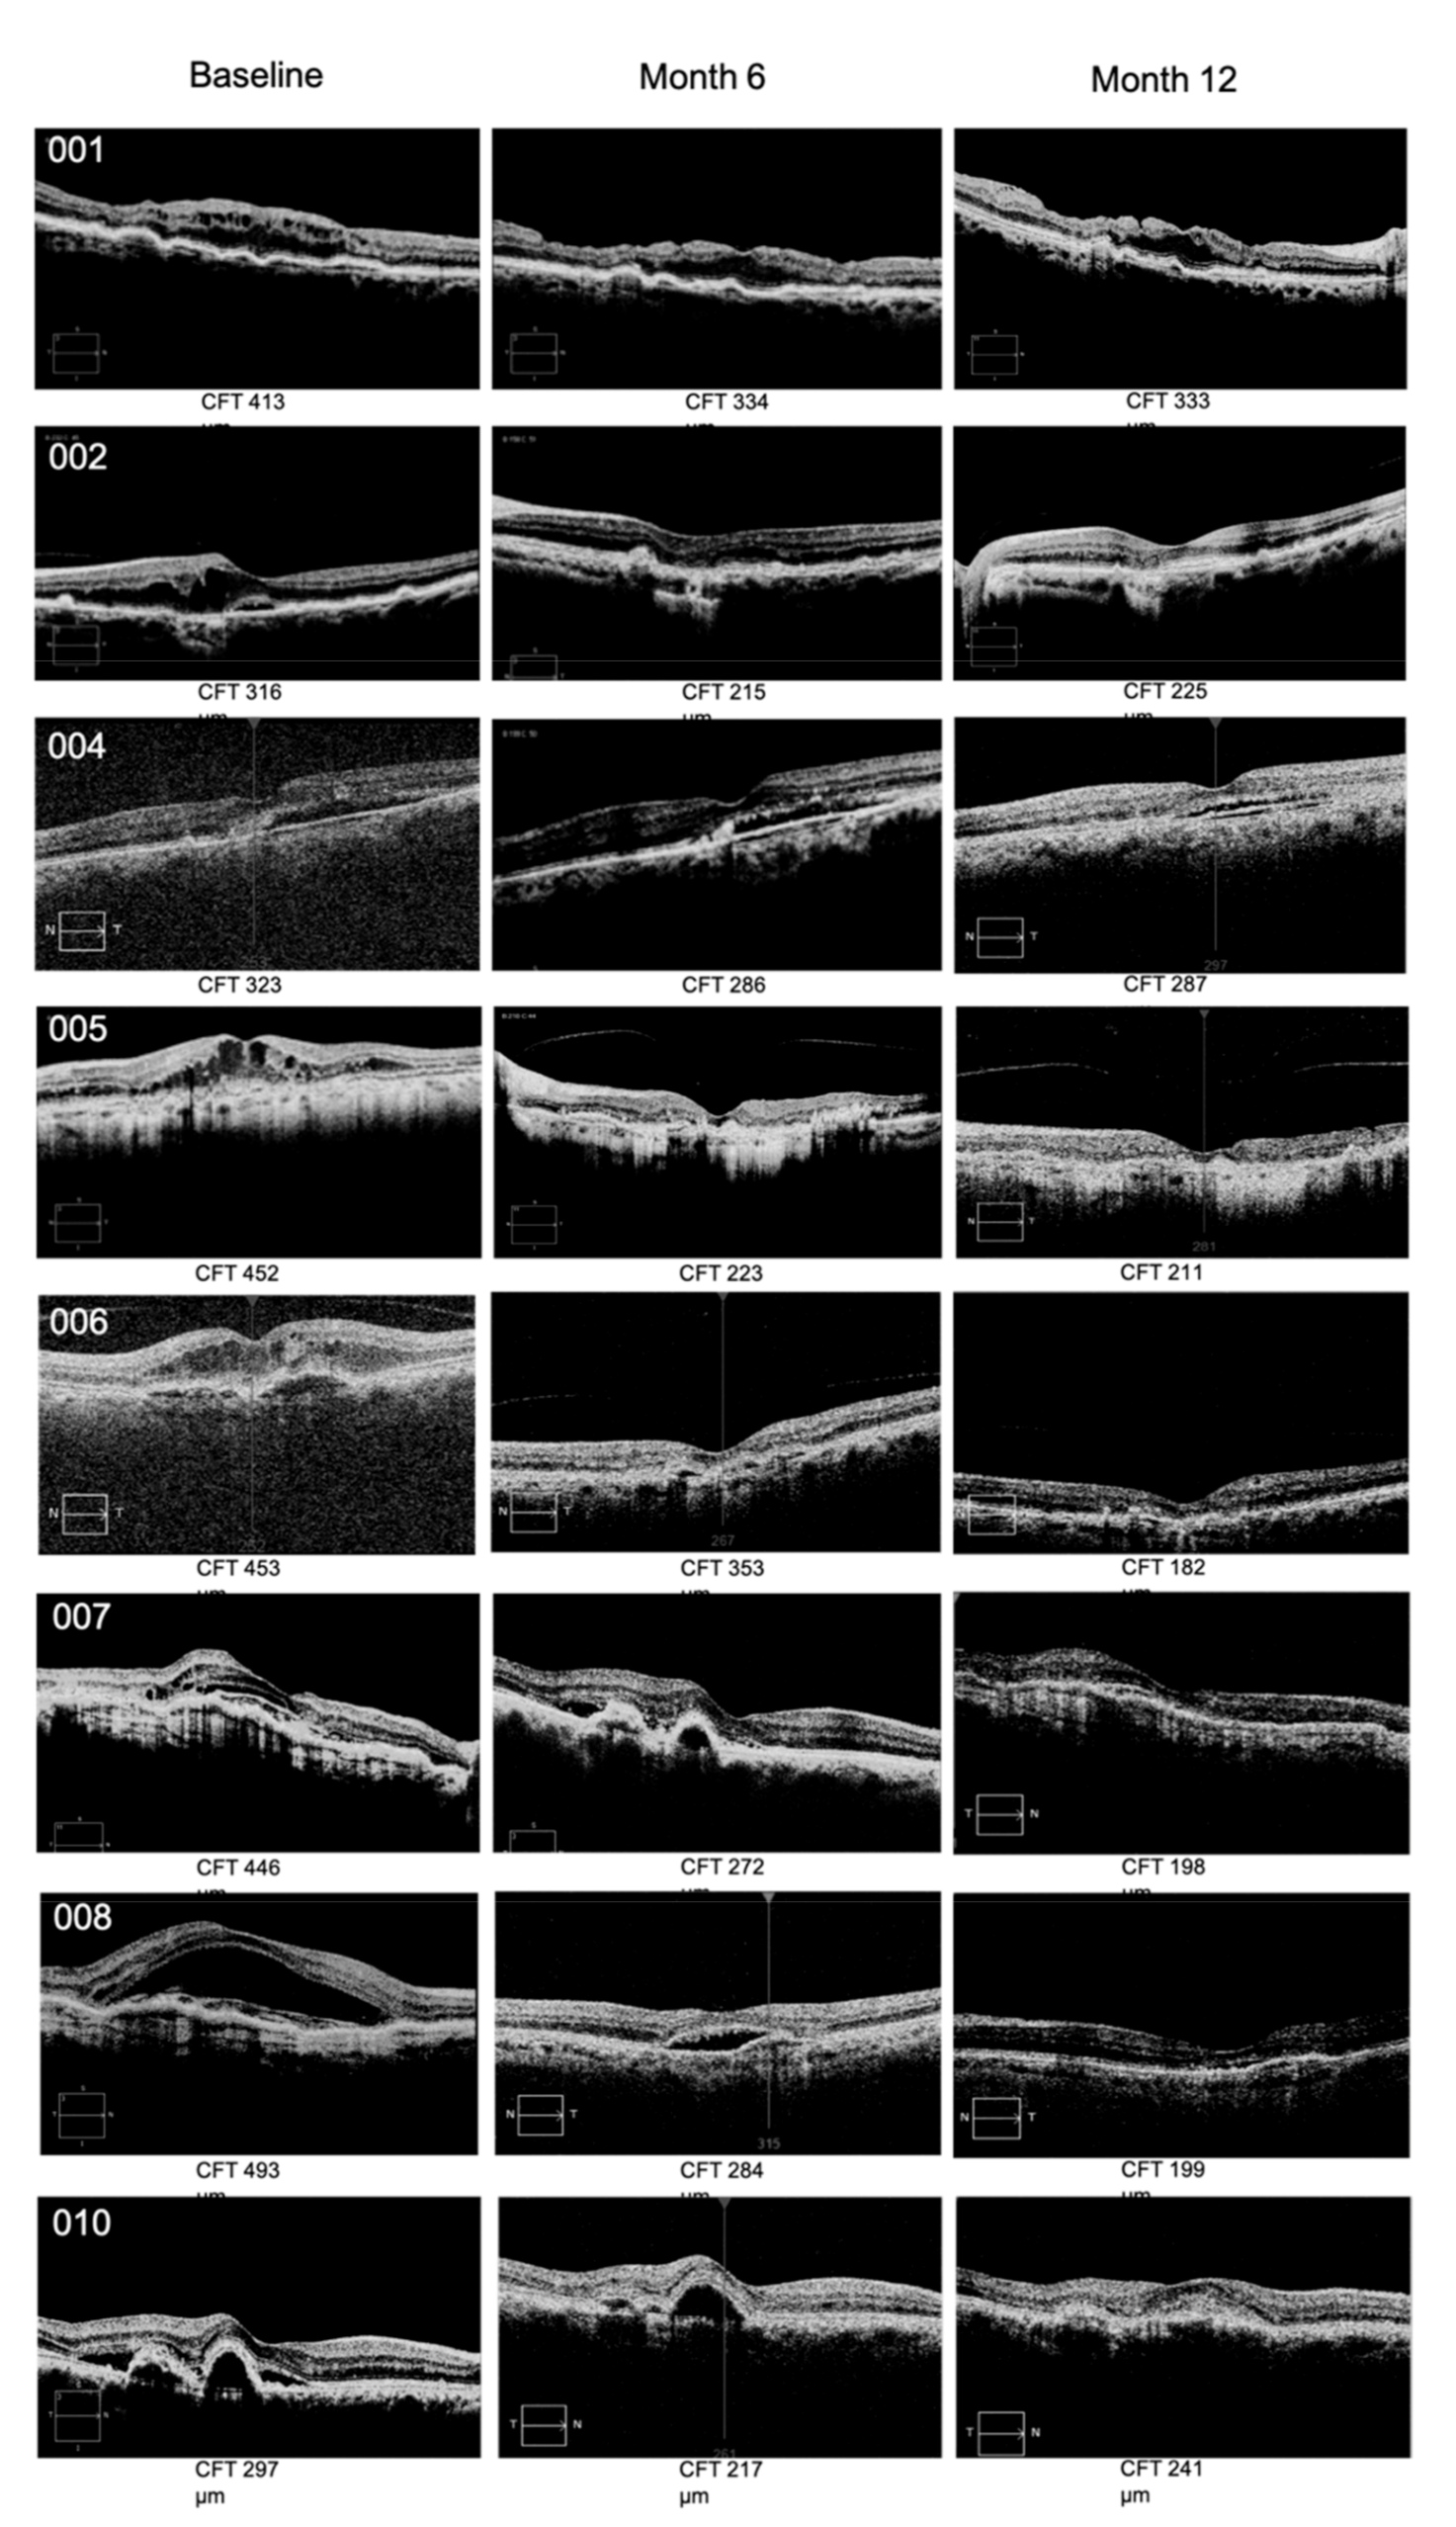

Relative to efficacy outcomes, in the RBZ-TALF group, we observed a significant improvement in BCVA and CFT. BCVA improved from 56.12 ± 14.76 at baseline to 67.1 ± 13.4 letters (p < 0.002) at the end of the follow-up period (Table 2 and Figure 1). All patients improved in at least five letters, and four of them improved in more than 15 letters from baseline. Four out of the eight patients that completed the follow-up period had a BCVA of 70 letters or better at month 12 of the evaluation. CFT improved from 369.1 ± 80.5 μm at baseline to 271.3 ± 82.9 μm (p < 0.03) at month 12 (Table 2 and Figure 1). Representative OCT images are presented in Figure 2. Representative images of fundus and fluorescein angiography studies are presented in Figure 3.

Figure 2.

Representative images of CFT by OCT at baseline, month 6, and month 12 of the follow-up period for subjects included in the RBZ-TALF group. All patients showed a consistent and progressive reduction in CFT by month 12. CFT, central foveal thickness; OCT, optical coherence tomography; RBZ, ranibizumab; TALF, triamcinolone acetonide-loaded liposome formulation.